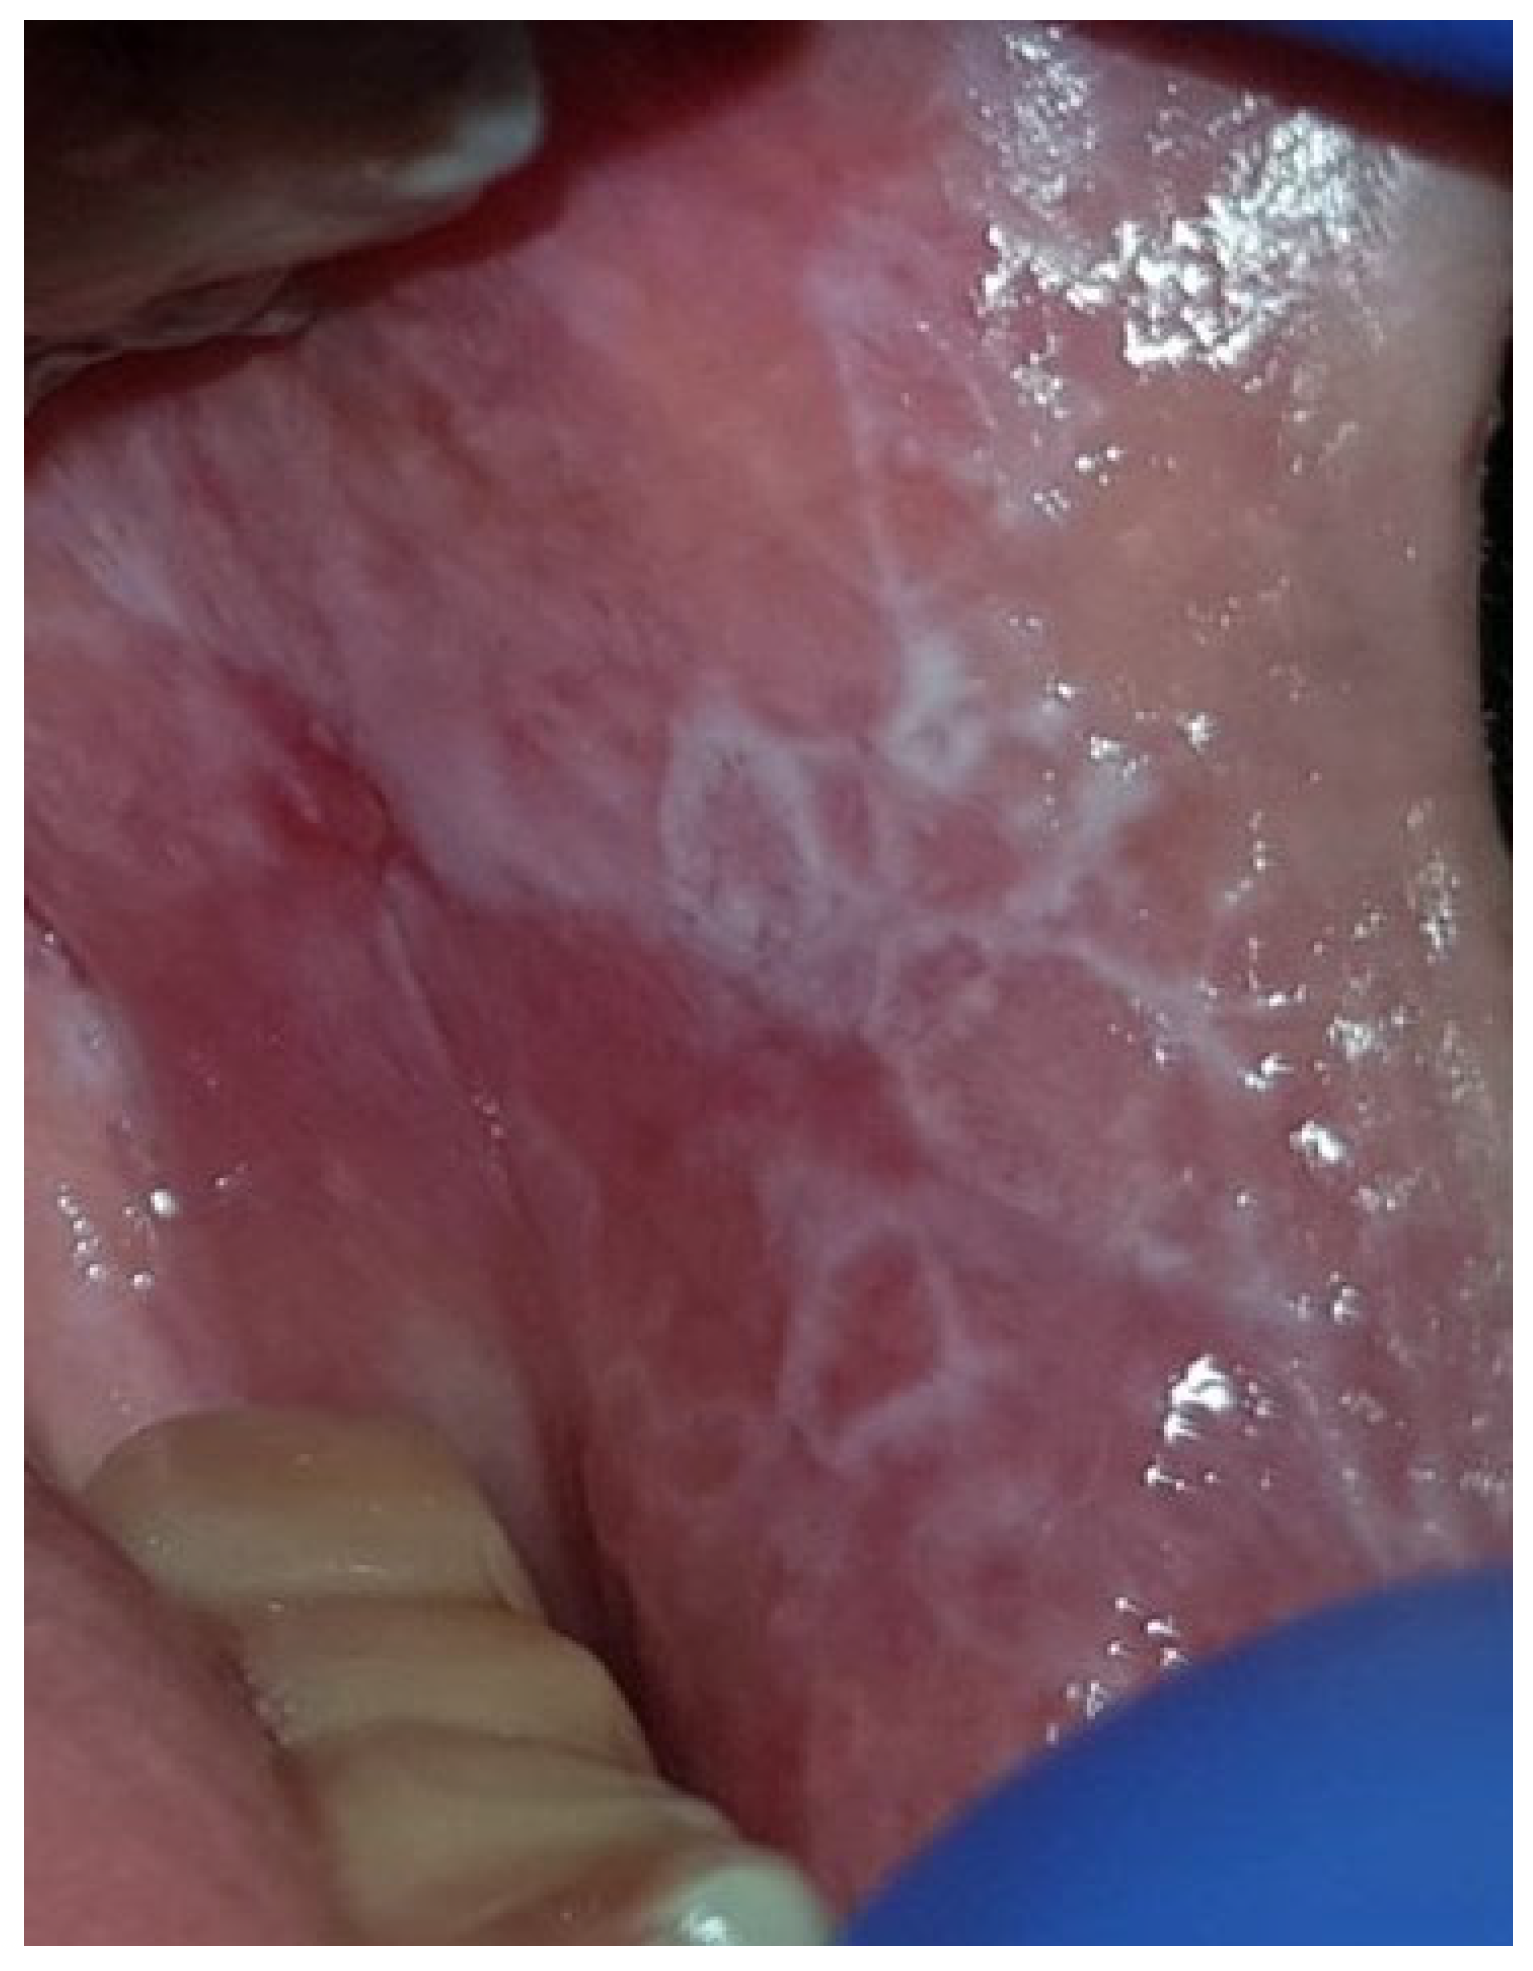

| The Clinical Form of OLP | Total (N = 186) | Females (N = 130) | Males (N = 56) | p | Smokers (N = 47) | Non-Smokers (N = 139) | p | Age Groups | p | ||

|---|---|---|---|---|---|---|---|---|---|---|---|

| <46 (N = 30) | 46–75 (N = 131) | >75 (N = 25) | |||||||||

| Reticular | 122 (65.6%) | 87 (66.9%) | 35 (62.5%) | 0.5623 | 33 (70.2%) | 89 (64.0%) | 0.4393 | 20 (66.7%) | 86 (65.5%) | 16 (64.0%) | 0.9784 |